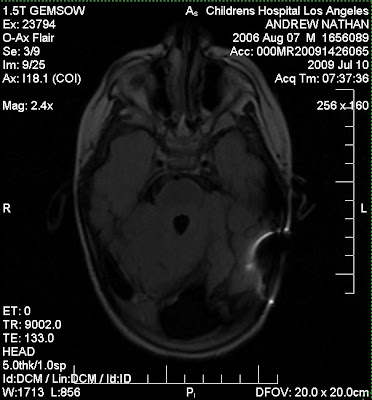

Talking about perspective, below are a few pictures of Nathan’s brain:

| From o-ax t1, flair |

When I look at these pictures it reminds me of just HOW amazing Nathan is. You don’t need to be a neuroscientist to see the abnormalities in his brain. This is a child with not only severe holoprosencephaly, he has suffered damage from hydrocephalus and bacterial meningitis. I can easily name 50 things wrong with his brain. And if I wanted to start labeling all of his diagnoses,well, it would be a long post indeed.